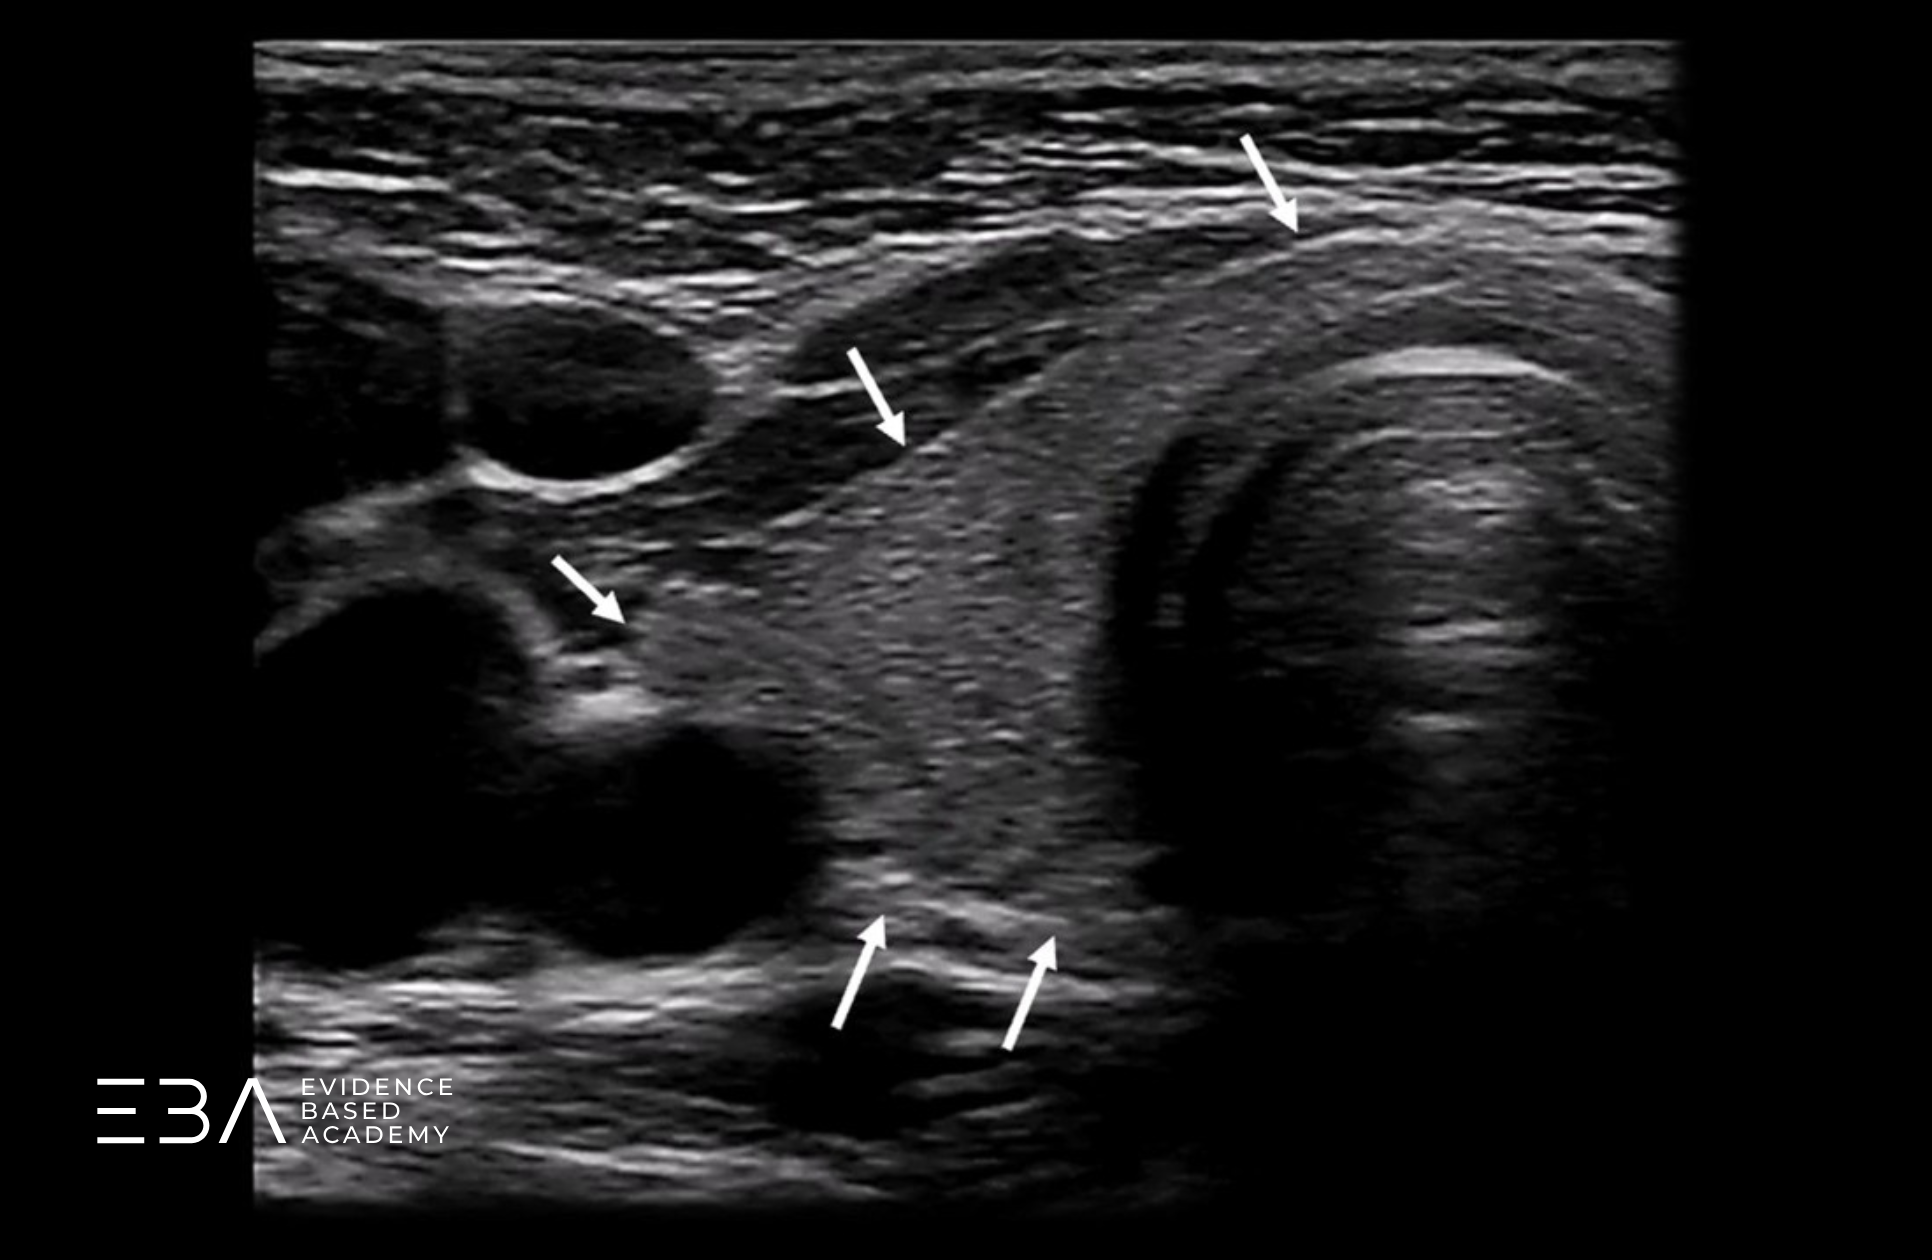

Poza znajomością prawidłowej anatomii tarczycy ważna jest również wiedza na temat jej otoczenia. Na poniższym schemacie oznaczyliśmy struktury sąsiadujące z tarczycą.

Schemat prawego płata z podpisami otaczających struktur.

Warto zwrócić uwagę na strukturę położoną grzbietowo do tarczycy, zwykle po lewej stronie szyi. Przełyk, bo o nim mowa, w projekcji poprzecznej może początkowo imitować zmianę ogniskową. Zmiana projekcji na podłużną pozwala uwidocznić jego charakterystyczny kształt i rozwiać wątpliwości.

Przełyk w projekcji poprzecznej i podłużnej.